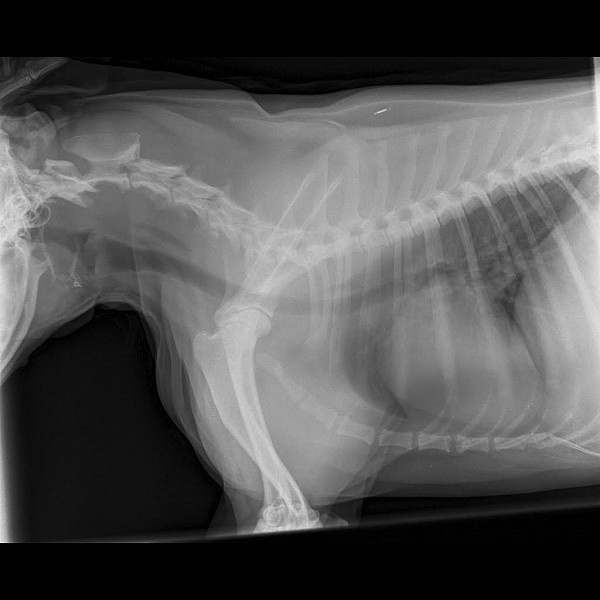

Рентгеновские снимки анатомии собак: строение и здоровье